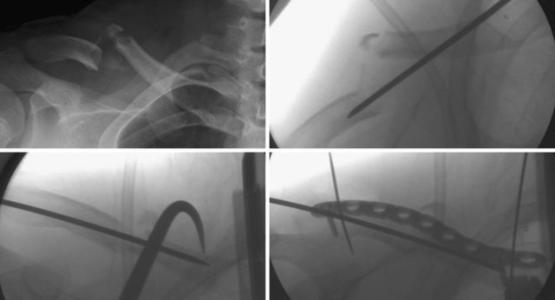

1.2治疗方式。对照组采用内固定术,以骨折部位为中心处, 在其外侧作一长约 10 cm 的纵行切口,将表层皮肤、皮下组织和深筋膜逐层切开,确保骨折端充分外露;清洗创口后予以解剖复位,剥离骨膜,加压钢板,用固定器进行固定,使用浓度为 0.9% 的氯化钠溶液冲洗创口,缝合伤口,给予适量抗生素类药物预防感染。观察组患者实施微创接骨板术,具体操作为:根据患者身体情况选择硬膜外麻醉或全身麻醉, 切开复位骨折部位,对胫骨骨折部位予以内固定术切开复位; 分离骨膜与骨膜外深筋膜;沿同一切口将经皮下组织隧道内径胫骨远端骨折解剖型钢板插入;将螺钉固定于骨折远端与近端切口处,另用螺丝钉对螺丝孔予以内固定。

微创接骨板术是一种在患者骨折部位行一小切口,搭建组织隧道,以最大限度减少骨折外露,对骨折予以间接固定的手术方式。与内固定手段相比,它可实现对骨折端骨膜与软组织最大程度的保护,减少对骨折部位血液运行状态的影响,从而提高骨折愈合速度,加快患者患者功能的恢复 [7]。从本次研究结果中可以看出,对照组患者治疗优良率为 75.0%,观察组患者治疗优良率为 93.8%,存在统计学方面的差异(P< 0.05); 对两组手术时间、术中出血量和住院时间等手术指标进行对比,存在统计学方面的差异(P<  0.05);对照组和观察组患者的不良反应发生率分别为 20.8% 和6.3%,差异有统计学意义(P<  0.05),所得结论证明微创接骨板术治疗四肢骨折效果明显。